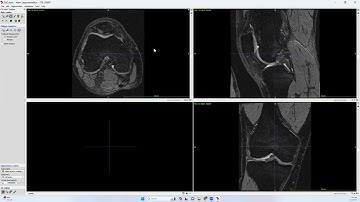

Psoas Segmentation in ITK SNAP